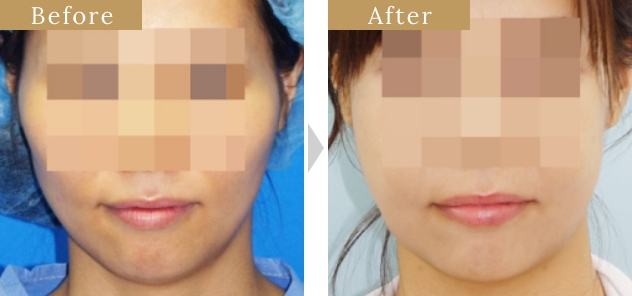

症例

『オトガイ形成骨切り術』の

特徴

骨切り量が非常に大きい

オトガイ神経を剥離して下顎骨を広範囲に露出し、神経の上下からアプローチするため、骨切り範囲がオトガイ部先端から下顎角直前におよび、切除幅8㎝~10㎝、全長14cm~16cmと非常に大きい。

スムーズなカーブラインの

骨切りが可能

骨切りカッターを垂直に骨に当てるため、下顎角直前までスムーズなカーブラインの骨切りが可能。

希望に応じた

Vラインのオトガイ形成

オトガイ部先端から下顎角直前までの広い範囲の骨切りによってシャープなVライン形成が可能。